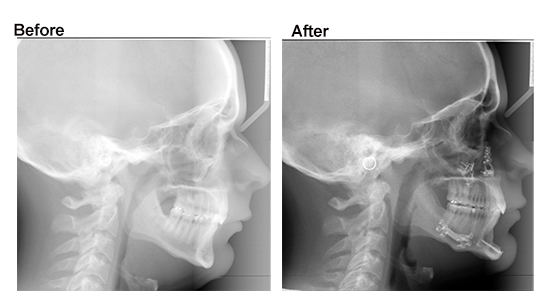

- Cephalometric X-rays

- Normal Jaw Surgery: Traditional surgical planning using physical models and 2D imaging. Effective, covered by insurance if medically necessary.

- X-rays (ceph + panoramic)